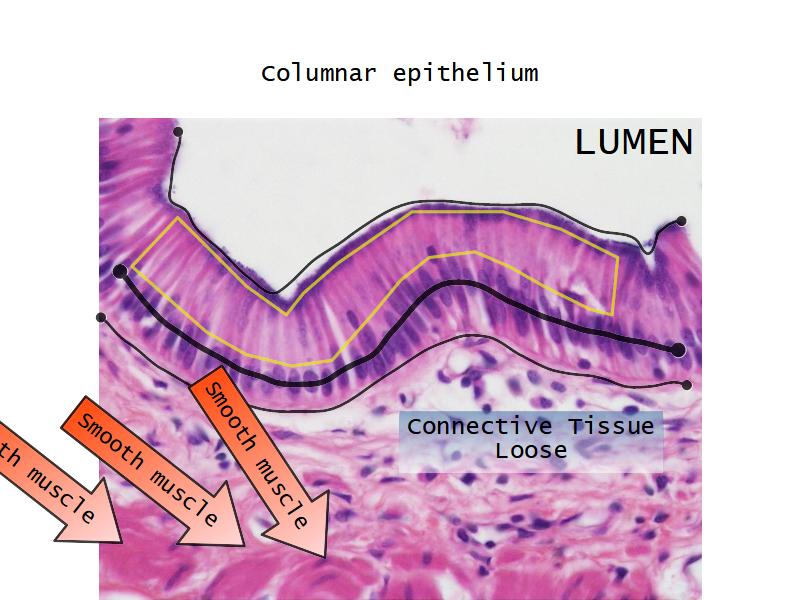

Respiratory epithelium

- Pseudostratified

- Ciliated

- Columnar

- Epithelium with

- 4 Cells

- Ciliated columnar cells

- Non-ciliated columnar cells

- Goblet cells

- Basal cells

Bronchi - Transitions

- Intrapulmonary bronchi

- Irregular cartilage

- Respiratory epithelium

- Glands

- Bronchioles

- Smooth muscle REPLACE cartilage

- Ciliated columnar > Ciliated cuboidal

- NO glands - goblet cells -> secretory cells